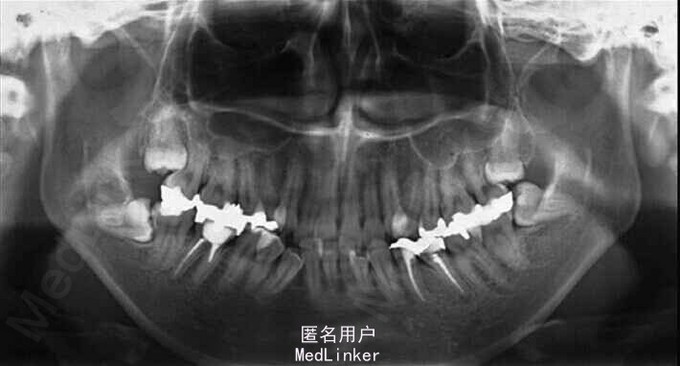

面部:凸面型,上下唇前突,上唇E线前3.5mm,下唇E线前9.5mm,闭唇时口周肌肉紧张。口内检查:双侧尖牙磨牙I类关系,左侧7锁合,覆盖4.5mm,覆合1mm,中线正,上颌拥挤度12.5mm,下颌拥挤度8.2mm。全景片示4个第三磨牙均阻生,怀疑上颌第二磨牙远中面因8阻生有牙根吸收,下颌8近中倾斜阻生更严重,右下6、左下4和5都行了RCT并大面积充填。头影测量示骨性I类,高角,下切牙唇倾。无TMJ症状,只是咀嚼测试时,右侧(非锁合侧)较左侧速度更快且更稳定。

诊断:安氏II类1分类,双颌前突,牙列严重拥挤,左下7锁合,双侧上7牙根吸收,四颗第三磨牙阻生 治疗目标:减少唇的突度及前牙拥挤,扶正4颗阻生的第三磨牙,达到良好的面部美观和功能咬合。 治疗:上颌拔除2颗5和2颗7(不拔4的原因为左上4为正常牙,左上5大面积充填;右上4形态较右上5好。因拔除了坏牙保留了健康牙齿,但是拔5不利于前牙的内收,所以于上后牙56之间植入了支抗钉加强支抗,辅助内收前牙。拔7原因为两颗7远中面均有牙根吸收且有大面积充填),下颌左侧拔除5和7(左下5根管治疗且根尖阴影,拔除左下7原因为严重锁合,改正困难且容易导致上下磨牙的伸长加重II类高角面型),右侧拔除根管治疗且大面积充填后的6;分别竖直4颗近中倾斜阻生的8,整个疗程39个月,四颗8成功的代替6或7。双侧I类尖牙关系,左侧磨牙I类关系,右侧磨牙完全远中关系。唇突度改善,全景片可见达到可接受的牙根平行度,4个8完全萌出直立。以前因为锁合导致的两侧咬合不对称没有了。